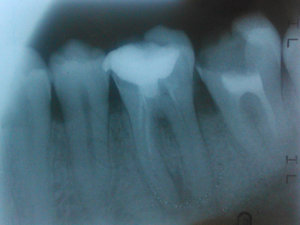

Отвалилась старая пломба, которую ставили девять лет назад. Пришел к стоматологу, она осмотрев сказала, что надо зачистить и заново запломбировать. Начав процедуру чистки, она попробовала пошатать зуб, потом сказала, что нужно сделать снимок. Снимок сделали, ее вердикт — надо удалять зуб, поскольку пошло воспаление вокруг корней, если его лечить со штифтами или еще как, через некоторое время он снова даст о себе знать и все равно придется удалить.

Есть ли смысл обратиться к другому специалисту? Или поверить и удалить?

Смысл конечно всегда есть, но если диагноз доктора подтвердится (воспаление на корнях), то скорее всего зуб придётся удалить.